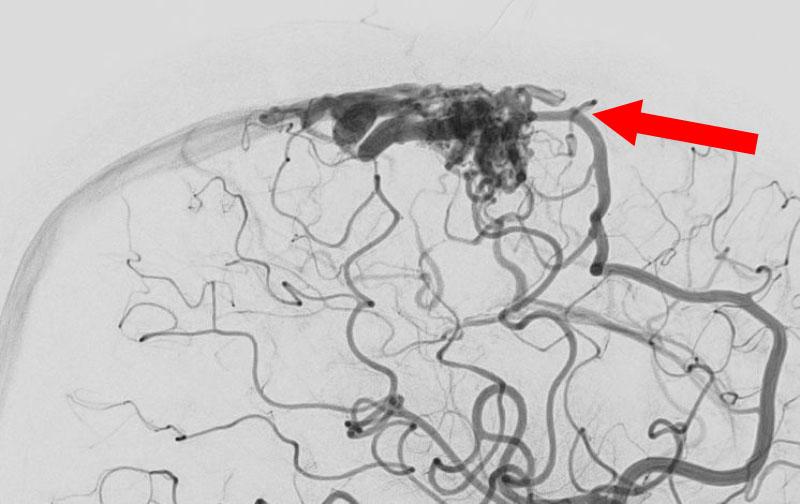

1585

'25年10月6日

脳動静脈奇形

50代

大阪府の病院

後

治療